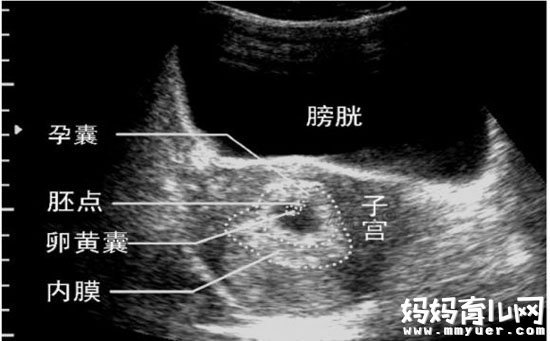

孕囊只在怀孕早期见到。月经28~30天规则来潮的妇女,停经35天,B超就可以在宫腔内看到孕囊。在怀孕6周时孕囊直径约2厘米,孕10周时约5厘米。

孕囊位置在子宫的宫底、前壁、后壁、上部、中部都属正常;形态圆形、椭圆形、清晰为正常;如孕囊为不规则形、模糊,且位置在下部,孕妇同时有腹痛或阴道流血时,可能要流产。